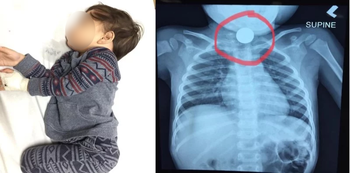

Batang nakalunok ng barya

Isang bata sa Malaysia ang nakalunok ng barya. Ngunit bago matanggal ito at tuluyang mailigtas ang bata ay dumaan pa ang 24 oras. Ito ay dahil sa kakulangan ng maayos na medikal na pasilidad sa kanilang lugar.

Bandang 11:30 ng gabi ay napagdesisyunan na ng mag-asawa na dalhin ang kanilang anak sa clinic. Ngunit sira ang x-ray machine ng unang clinic na kanilang napuntahan. Kaya agad silang lumipat ng isa pang clinic na kung saan doon nila nalaman na may barya palang nakabara sa lalamunan ng kanilang anak. Pero hindi daw kayang tanggalin ng clinic ang baryang nakabara sa lalamunan ni Reza. Dahil sila ay walang tamang equipment para gawin ito. Kaya naman lumipat muli sila sa isang ospital na kung saan ang sabi sa kanila ng nurse na sila ay puno at hindi ma-accommodate ang anak niya. Ngunit maliban dito napag-alam nilang wala palang child surgeon sa ospital na kayang magsagawa ng operasyon sa kanilang anak.

Bandang alas-5 ng madaling araw nilagay na sa critical zone si Reza dahil hirap na hirap na siyang huminga. Mabuti nalang sa huling ospital na kanilang napuntahan na matatagpuan sa Kuala Lumpur ay naasikaso na ng maayos ang bata.

Dahil sa may mga bagay na dapat isaalang-alang, si Reza ay naoperahan ng bandang 10 ng gabi. Ngunit naging matagumpay naman ito at natanggal ang baryang nakabara sa lalamunan niya.